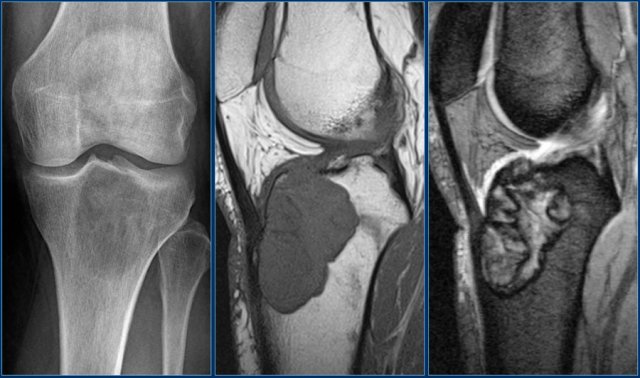

ABC (8)

On the left another ABC, located in the distal femur.

The plain radiograph shows a layered periosteal reaction and Codman triangle in direct relationship to an expansile lytic lesion with a thin peripheral bone shell.

CT also reveals the subperiosteal origin of the lesion with secondary involvement of the cortical bone.

Axial T2-weighted image with fatsat and contrast enhanced T1-weighted image with fat sat show multiple fluid-fluid levels with rim enhancement of the cavities filled with blood.

This is typical for an aneurysmal bone cyst.